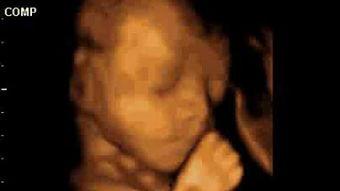

- 胎儿胎动:对于准妈妈来说,看到胎儿的胎动,是一种无比幸福的感觉。彩超视频可以捕捉到胎儿在母体内的每一个小动作。

- 妇产科:用于监测胎儿发育情况,检查胎盘、羊水、脐带等。